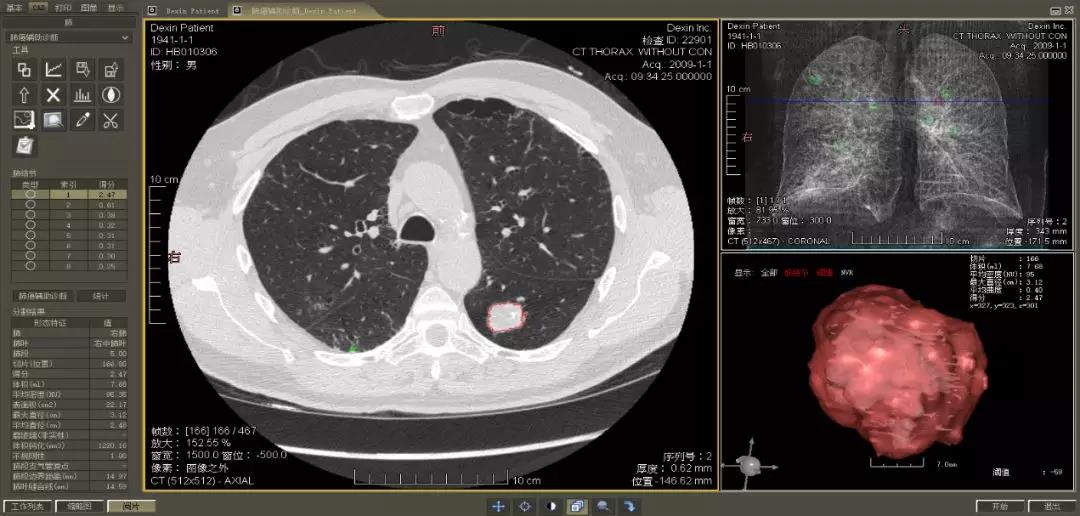

▲ 數(shù)字肺產(chǎn)品肺癌計算機(jī)輔助診斷

醫(yī)療影像智能分析是指運用人工智能技術(shù)、計算機(jī)視覺技術(shù)以及計算幾何技術(shù)對醫(yī)療影像進(jìn)行自動分析,幫助醫(yī)生定位病癥、分析、跟蹤病情,并通過量化數(shù)據(jù)輔助醫(yī)生做出診斷,目前其旗艦產(chǎn)品“數(shù)字肺”已經(jīng)覆蓋多種肺部疾病的早期檢測、診斷、跟蹤、術(shù)前規(guī)劃等完整的醫(yī)療流程。在臨床實踐中,超過80%的醫(yī)療數(shù)據(jù)來自醫(yī)療影像,這些影像數(shù)據(jù)通常需要專業(yè)醫(yī)生進(jìn)行解讀,工作的重復(fù)性高、效率偏低。如果能夠運用智能影像分析技術(shù),同時結(jié)合臨床表現(xiàn)以及既往病例進(jìn)行全面分析,那么就可以大幅度提升影像診斷效率和準(zhǔn)確性,讓專業(yè)醫(yī)生的寶貴時間集中在復(fù)雜病情的診斷和治療等環(huán)節(jié)。